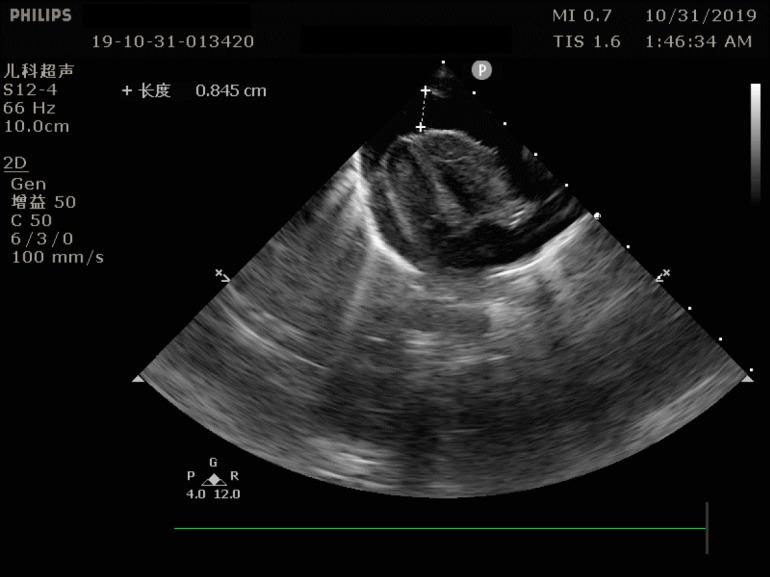

CASE SUMMARY

A neonate weighting 2.8 kg was born at 40 wk of gestation. He was admitted to the Surgery Intensive Care Unit due to suspected congenital megacolon. A PICC line was inserted via the left antecubital fossa for the administration of total parenteral nutrition. Three days later, the patient was still on total parenteral nutrition. Cardiac tamponade caused by PICC was found on ultrasound. The patient recovered spontaneously after an emergency pericardiocentesis.

一名体重2.8千克的新生儿在妊娠40周时出生。因疑似先天性巨结肠入住外科重症监护病房。经左肘前窝插入一根PICC导管用于全胃肠外营养。三天后,患者仍在接受全胃肠外营养。超声检查发现由PICC导致的心脏压塞。紧急心包穿刺术后患者自行康复。